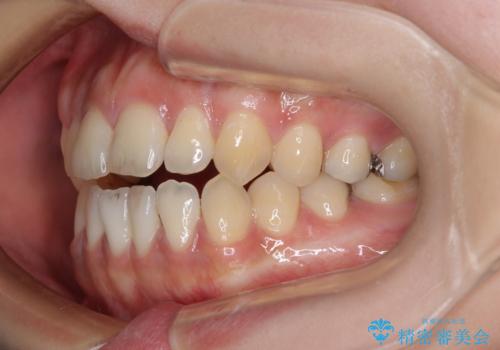

開咬をワイヤー装置で矯正治療

- 上下前歯が非接触となっている咬み合わせを気にして来院された患者様です。

治療開始から8ヶ月ほどで遠方への転勤が決まりましたが、歯列は概ね整っていたため、その後は東京出張を狙って治療を終える処置を行うことができました。